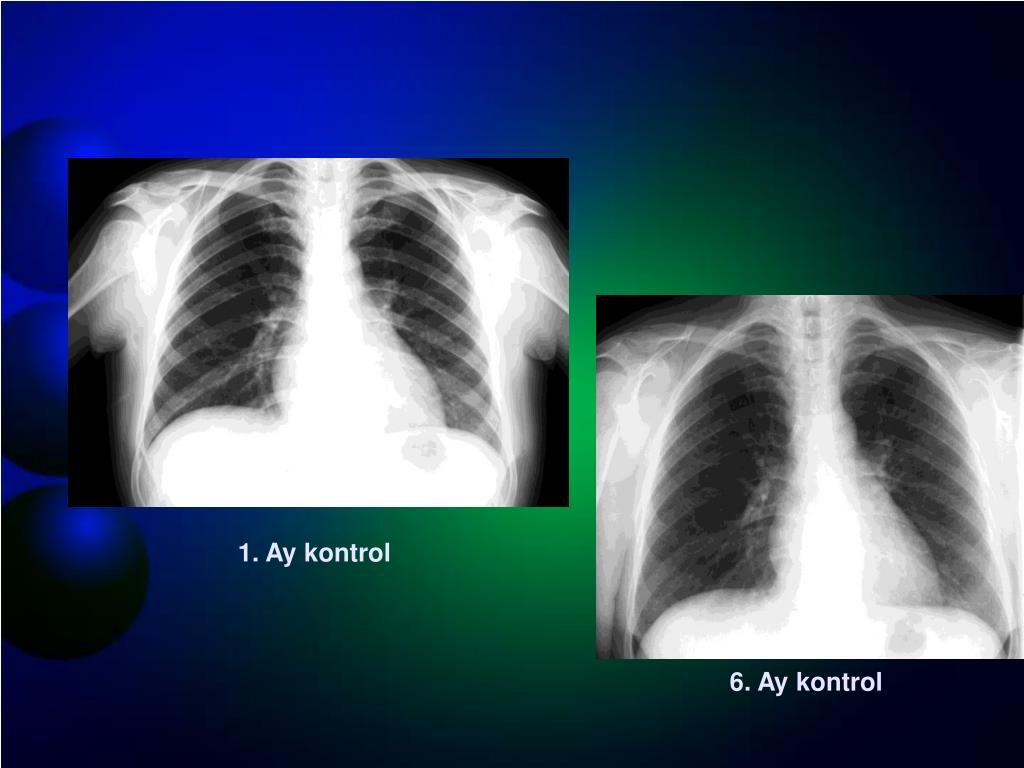

31. 35 yaşında kadın olgu 10 günlük yüksek ateş, titreme, güçsüzlük, gece terlemesi 2 gündür ağır dispne 1 ayda 7 kg vermiş 6 yıl önce hipertiroidi tanısı var-PTU kullanıyor Beta bloker alıyor Antidepresan alıyor DAH-PTU

32. 1. Ay kontrol 6. Ay kontrol